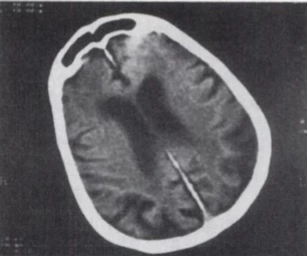

CT.PNG 잔 칼망의 CT 사진(출처: Karent Ritchie, 아래 논문)

잔 칼망의 개인적인 생활이 세상에 알려지기 시작한 건 그녀가 110살 이후. 즉, 지나치게 늙은 이후라는 점을 간과할 수 없다. 그러나 의학적으로 그녀의 정신건강을 검진한 결과도 살펴야 한다. 잔이 118살이 됐을 무렵, 정신과 의사 카렌 리치Karen Ritchie는 'Mental Status Examination of an Exceptional Case of Longevity'를 제목으로 잔의 정신 건강을 의학적으로 분석한 글을 내놓는다. 논문에 따르면, 잔은 118살임에도 불구하고, 고학력자인 80대와 비슷한 수준의 지능과 언어능력을 가졌다고 한다. 어휘 선택에 약간의 문제가 있었지만, 정신 의학적 측면에서는 어떠한 문제도 발견되지 않았다고 한다. 되려 테스트가 진행된 6개월 동안 잔의 지적 및 언어능력은 향상되기도 했다. 잔의 미심쩍은 발언들이 슈퍼센터네리언이라고 마냥 덮어둘 수 없는 이유다.